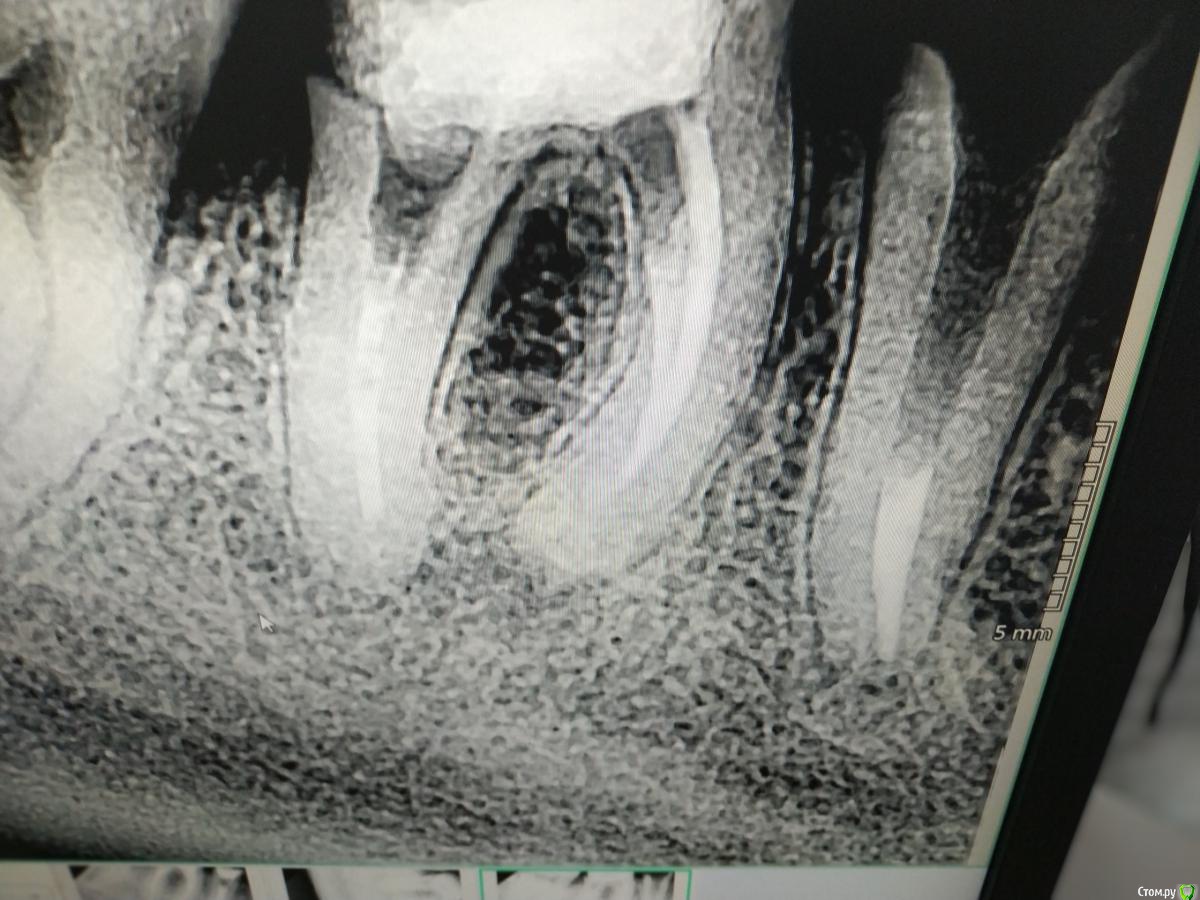

kuziy12 Опубликовано 20 июля, 2019 Автор Поделиться Опубликовано 20 июля, 2019 (изменено) Лето, хорошо... Начнем с хорошего..Жесть чуть позже. Обратилась женщина с 4.5, 4.6. Рекомендовал удалить 4.5, туда имплантация, 4.6 пробовать сохранять. Решили сохранять оба.Изначальная ситуация: Распломбировка, обработка машинными: 4.5 - до 30.04, .4.6 - до 25.04. Пульпосептин на 3 дня, пломбировка, культевая в 4.5, в 4.6 штифт и пломба. Дальше коронки МК связанные между собой. Надеюсь укрепит 4.5. Переживаю больше за его тонкие стенки. В храм сходил - свечку поставил. Вопрос: на сколько по времени ставите пульпосептин(если пользуетесь) при пульпитах, хронических, обострениях? Изменено 20 июля, 2019 пользователем kuziy12 Ссылка на комментарий

vse32 Опубликовано 20 июля, 2019 Поделиться Опубликовано 20 июля, 2019 Если честно, очень переживаю за бифуркацию 46. Думаю, через год вы там увидите неприятное разряжение. Тьфу-тьфу-тьфу конечно. Так что для меня тут более слабое звено 46, а не 45. Ссылка на комментарий

vse32 Опубликовано 20 июля, 2019 Поделиться Опубликовано 20 июля, 2019 Вы не поняли. Я не про то сейчас мне видится из-за жёсткости или резкости. А из-за очень тонкого дна полости зуба, отделяющего ее от фурки. Обычно там уже все сильно инфицирование. Что впоследствии даёт проблемы - разряжение в бифуркации Ссылка на комментарий

kuziy12 Опубликовано 20 июля, 2019 Автор Поделиться Опубликовано 20 июля, 2019 (изменено) Вы не поняли. Я не про то сейчас мне видится из-за жёсткости или резкости. А из-за очень тонкого дна полости зуба, отделяющего ее от фурки. Обычно там уже все сильно инфицирование. Что впоследствии даёт проблемы - разряжение в бифуркацииПонял вас. Но тут аргумент: с такими зубами, как на первом снимке она ходила 1.5 года. Не знаю только в пользу он или нетP/s: в л.с написал вам Изменено 20 июля, 2019 пользователем kuziy12 Ссылка на комментарий